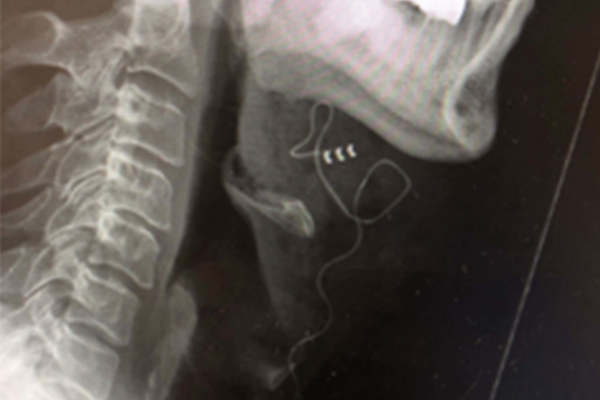

First UK hypoglossal nerve stimulation implant in the treatment for moderate to severe OSA